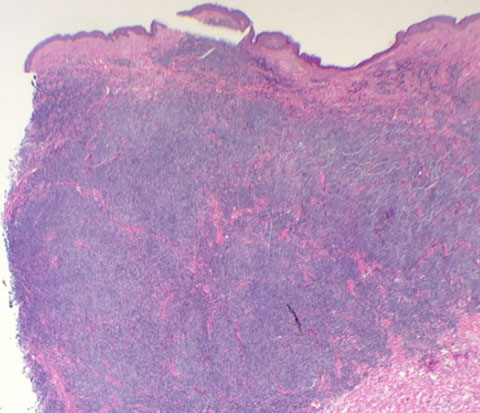

Micro: LN c diffuse nodal involvement showing pseudofollicular architecture (no true mantle zone) c large pale prolif centers c prolymphocytes (>11%; sm to med size cells c clumped chromatin and small nucleoli), paraimmunoblasts (larger, c round to oval nuclei, central red nucleoli)

Smudge cells seen in PB with small lymphs c clumped chromatin and round nuclei

- can see prolif of small, mature lymphs c multiple prolif centers / pseudofollicles